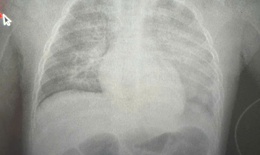

Bệnh trẻ em - 21/10/2025 14:34SKĐS - Viêm phổi là bệnh lý nhiễm trùng phổ biến, gây tổn thương nhu mô phổi và đi kèm các triệu chứng như ho, khó thở, nhịp thở nhanh, đau ngực…Bệnh có tỷ lệ mắc và tử vong cao, đặc biệt ở trẻ dưới 5 tuổi.

Triệu chứng viêm phổi ở trẻ sơ sinh

Bệnh trẻ em - 06/07/2025 17:24SKĐS - Viêm phổi là một bệnh truyền nhiễm, tấn công trực tiếp vào phổi và gây viêm. Đây là bệnh hô hấp nguy hiểm, đặc biệt là với trẻ sơ sinh. Việc nhận biết sớm và phát hiện mức độ nguy hiểm của bệnh để đưa trẻ đi viện điều trị kịp thời là vô cùng quan trọng.

Cấp cứu thành công trẻ 8 tháng tuổi bị sởi biến chứng nghiêm trọng

Y tế - 12/05/2025 06:48SKĐS - Mới đây, Bệnh viện Sản Nhi Vĩnh Phúc đã cứu sống trẻ bị sởi biến chứng rất nặng gây viêm phổi, suy hô hấp, ARDS, sốc nhiễm khuẩn...